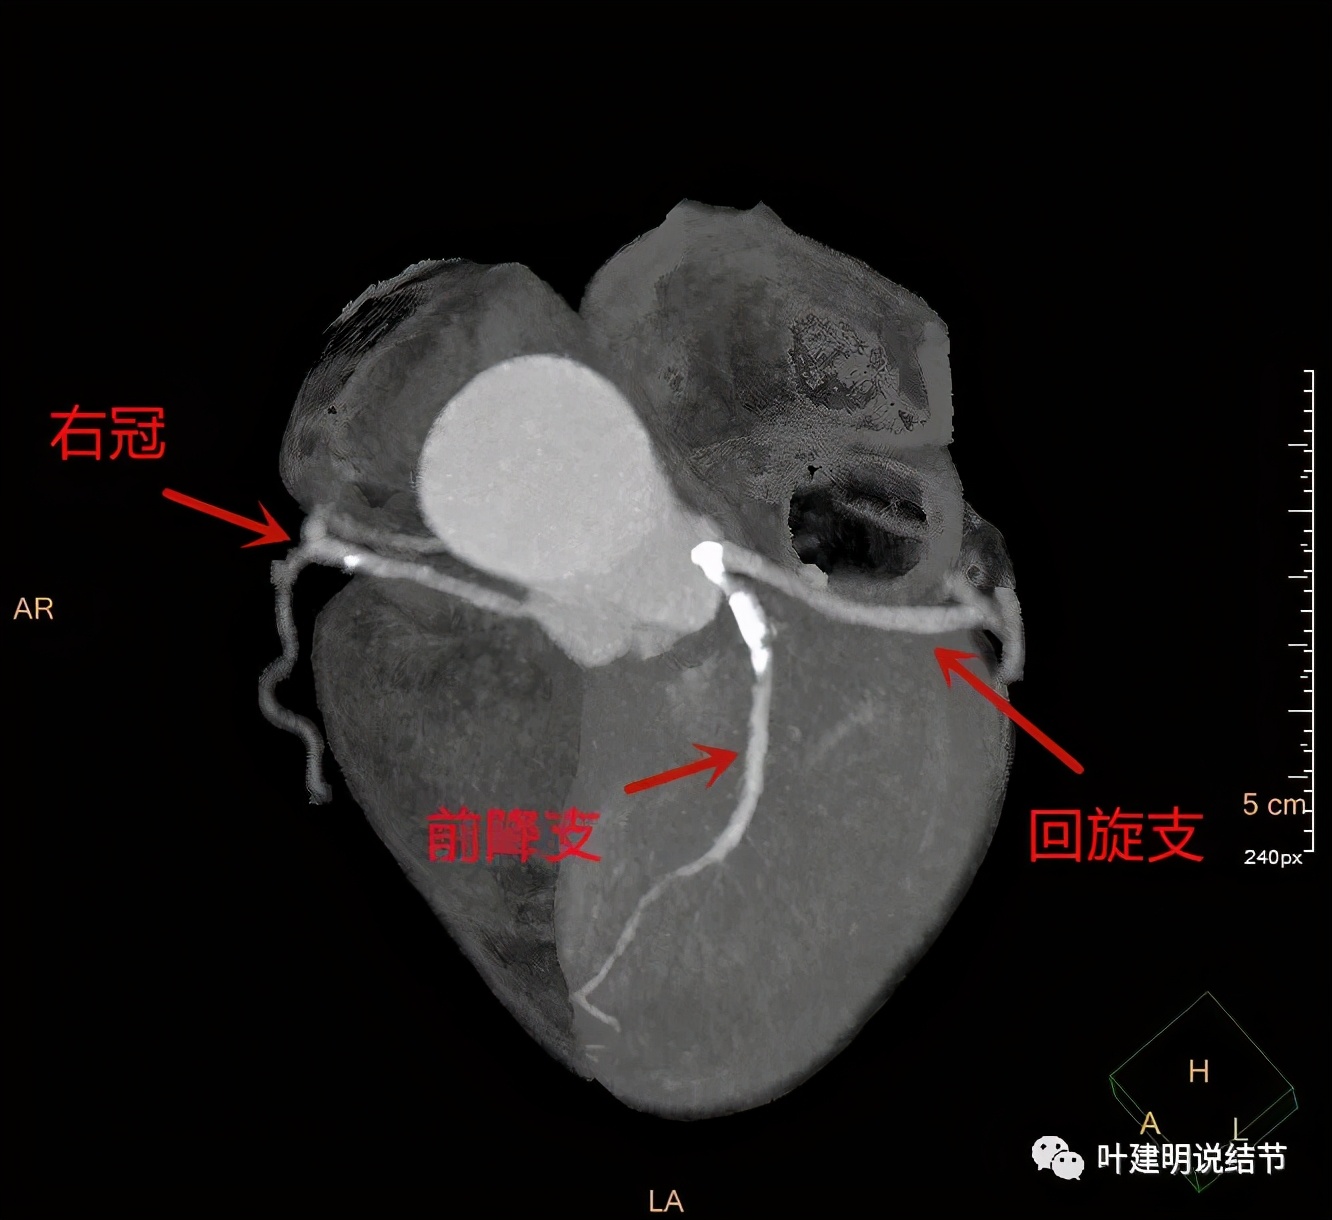

我们由胸顶再往颈部一层一层看,结果真的肿瘤是与右侧甲状腺相连的!那么应该可能是甲状腺来源的纵隔肿瘤(胸内甲状腺肿瘤)。这样的话,其他的边缘界限清楚,这种密度以结节性甲状腺肿可能性大,不太像甲状腺恶性肿瘤。那么与气管间估计也是紧密靠着而已,不会是侵犯的。所以我们商量后就不穿刺,打算直接手术切除。术前做了冠脉CT,也有点问题,好在冠脉狭窄程度不重: